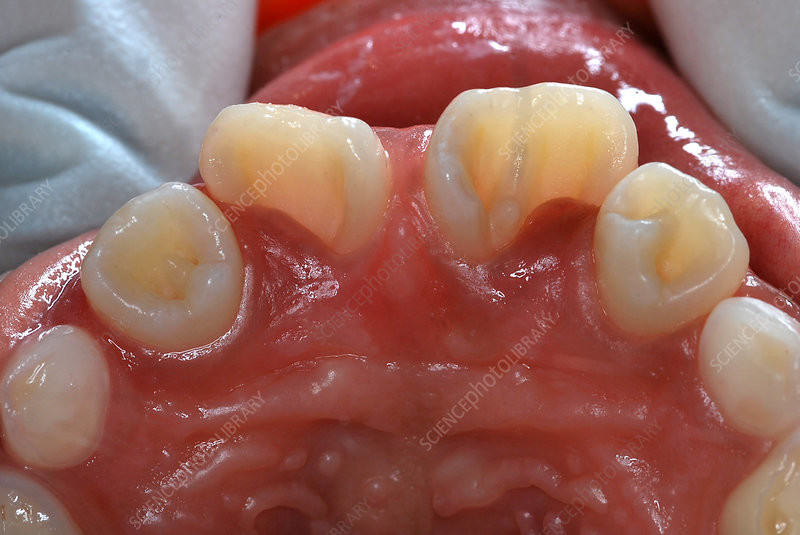

Dens invaginatus, or dens in dente (which translates to “tooth within a tooth”), is a dental anomaly. This condition occurs when the tooth’s enamel (the outer, visible layer of the tooth) folds into the dentin (the hard tissue beneath the enamel) during tooth development. This creates what looks like a small tooth within an existing tooth. Here, we’ll look at the symptoms and causes and what you can do if you have this condition.

According to the Journal of Oral Research and Review, dens in dente is rare, affecting between 0.3 percent and 10 percent of people. The maxillary lateral incisors (the pair of teeth on either side of the two front teeth) are most commonly affected by dens in dente, followed by the maxillary central incisors (the two front teeth). Researchers still aren't sure what causes this anomaly. Many theories have been proposed, including infection, pressure on the enamel, and trauma during tooth development. While you can’t prevent this condition from forming, you can consult your dental professional for a diagnosis and treatment.

Teeth affected by dens in dente may be malformed, wider, or peg-shaped. You may see what looks like a small tooth branching off a bigger tooth, though it may be difficult for a dentist to arrive at a definite conclusion during a regular oral exam. In fact, most teeth with this condition don’t show any signs of malformation on the outside. That’s why X-rays are most commonly used for a diagnosis, as the affected tooth may be asymptomatic. According to another report in the Journal of Conservative Dentistry, dental professionals may also use cone beam computerized tomography.